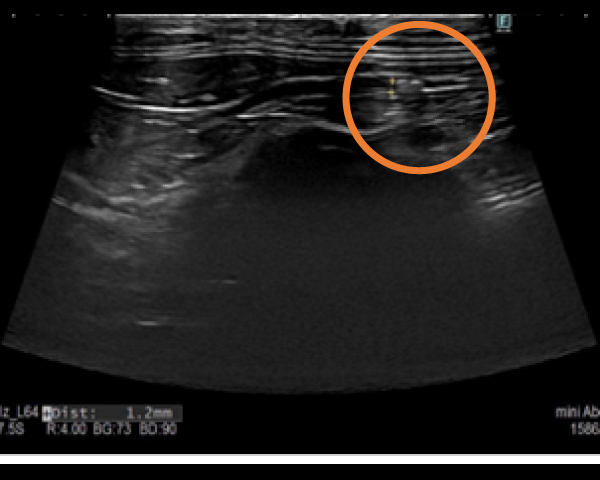

超音波にて結石を確認

手術に0.4mm結石を摘出